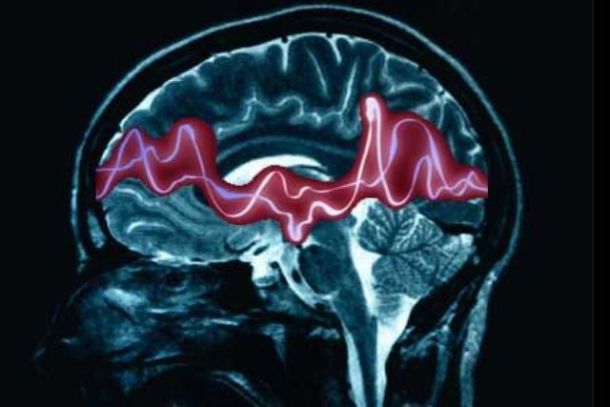

L’epilessia mioclonica corticale è caratterizzata da movimenti involontari ritmici alle estremità degli arti e frequenti crisi epilettiche. Fino a poco tempo le cause genetiche della malattia rimanevano ignote. Solo negli ultimi anni lo staff del San Raffaele, studiando una famiglia che presentava questa forma di epilessia, ha localizzato sul cromosoma 2 il gene che causa la malattia; ora questo gene è stato identificato. Si tratta del recettore che svolge un ruolo critico nella regolazione del rilascio di neurotrasmettitori.